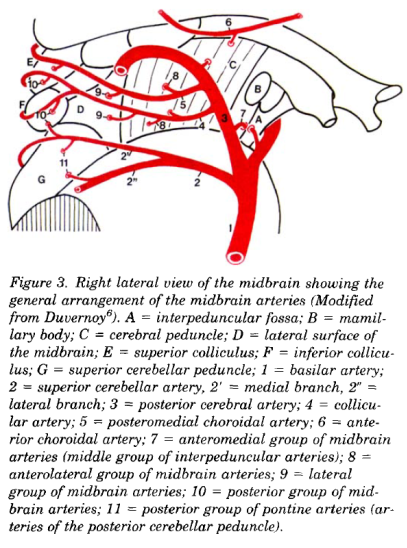

Cerebral vascular territories

Brainstem